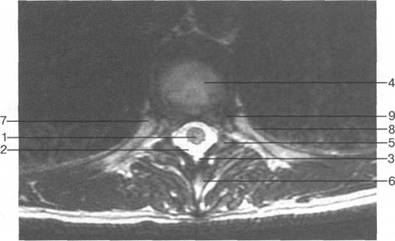

(dura mater spinalis), (arachnoidea spinalis) (pia mater spinalis).

(cavitas epiduralis),

Паутинная мозговая оболочка состоит из к 141s183b 83;еточной мембраны, к которой прикрепляется